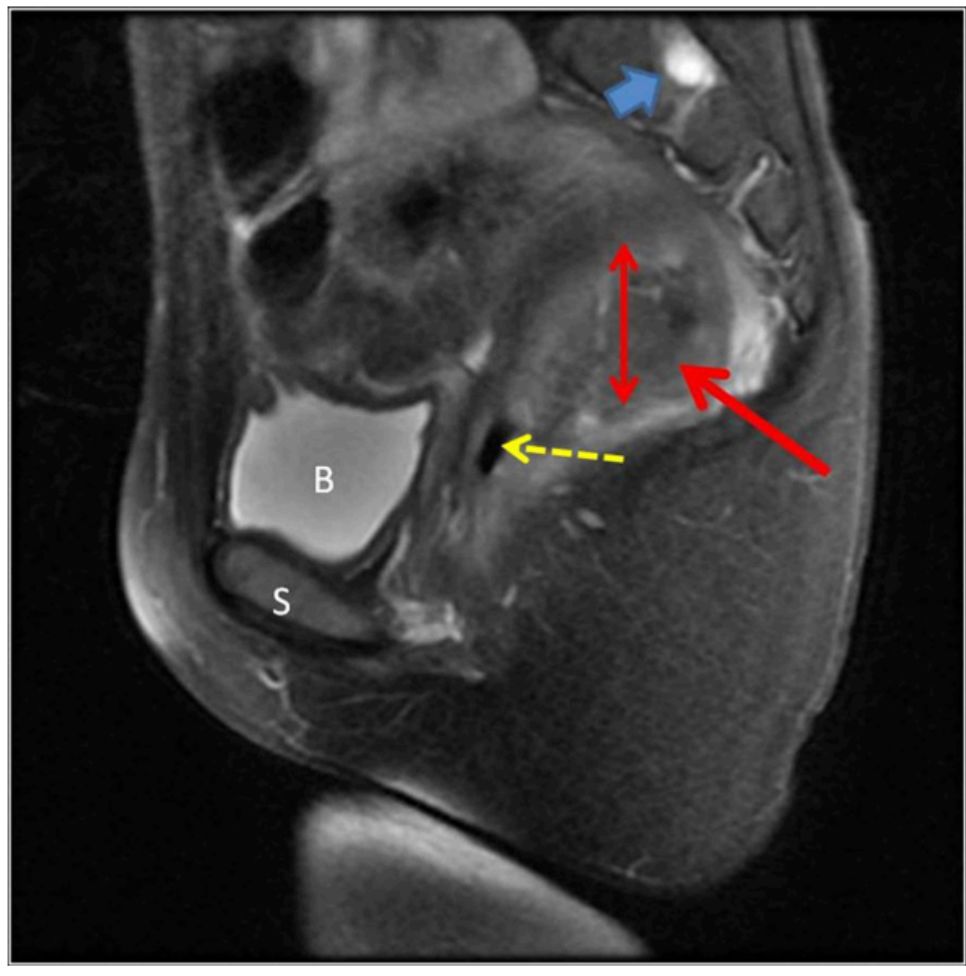

图4为骨盆磁共振成像的矢状面观。直肠管腔(虚线箭头)后的血肿(红色箭头)。偶发性tarlov囊肿(蓝色箭头)。B=膀胱,S=耻骨联合。